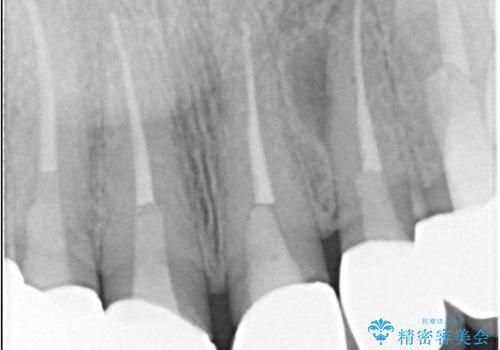

- 前歯の痛みと破折を主訴にご来院されました。精密な診査の結果、歯の根元までひび割れが進行し、保存が困難であると診断。見た目にも関わる前歯を失うことへの患者様の不安を考慮し、抜歯と同時にインプラントを埋入する抜歯即時埋入インプラントによる治療計画を立案しました。これにより、歯がない期間を最小限に抑え、治療期間と身体への負担を軽減しながら、審美性の高い新しい歯を獲得することを目指します。